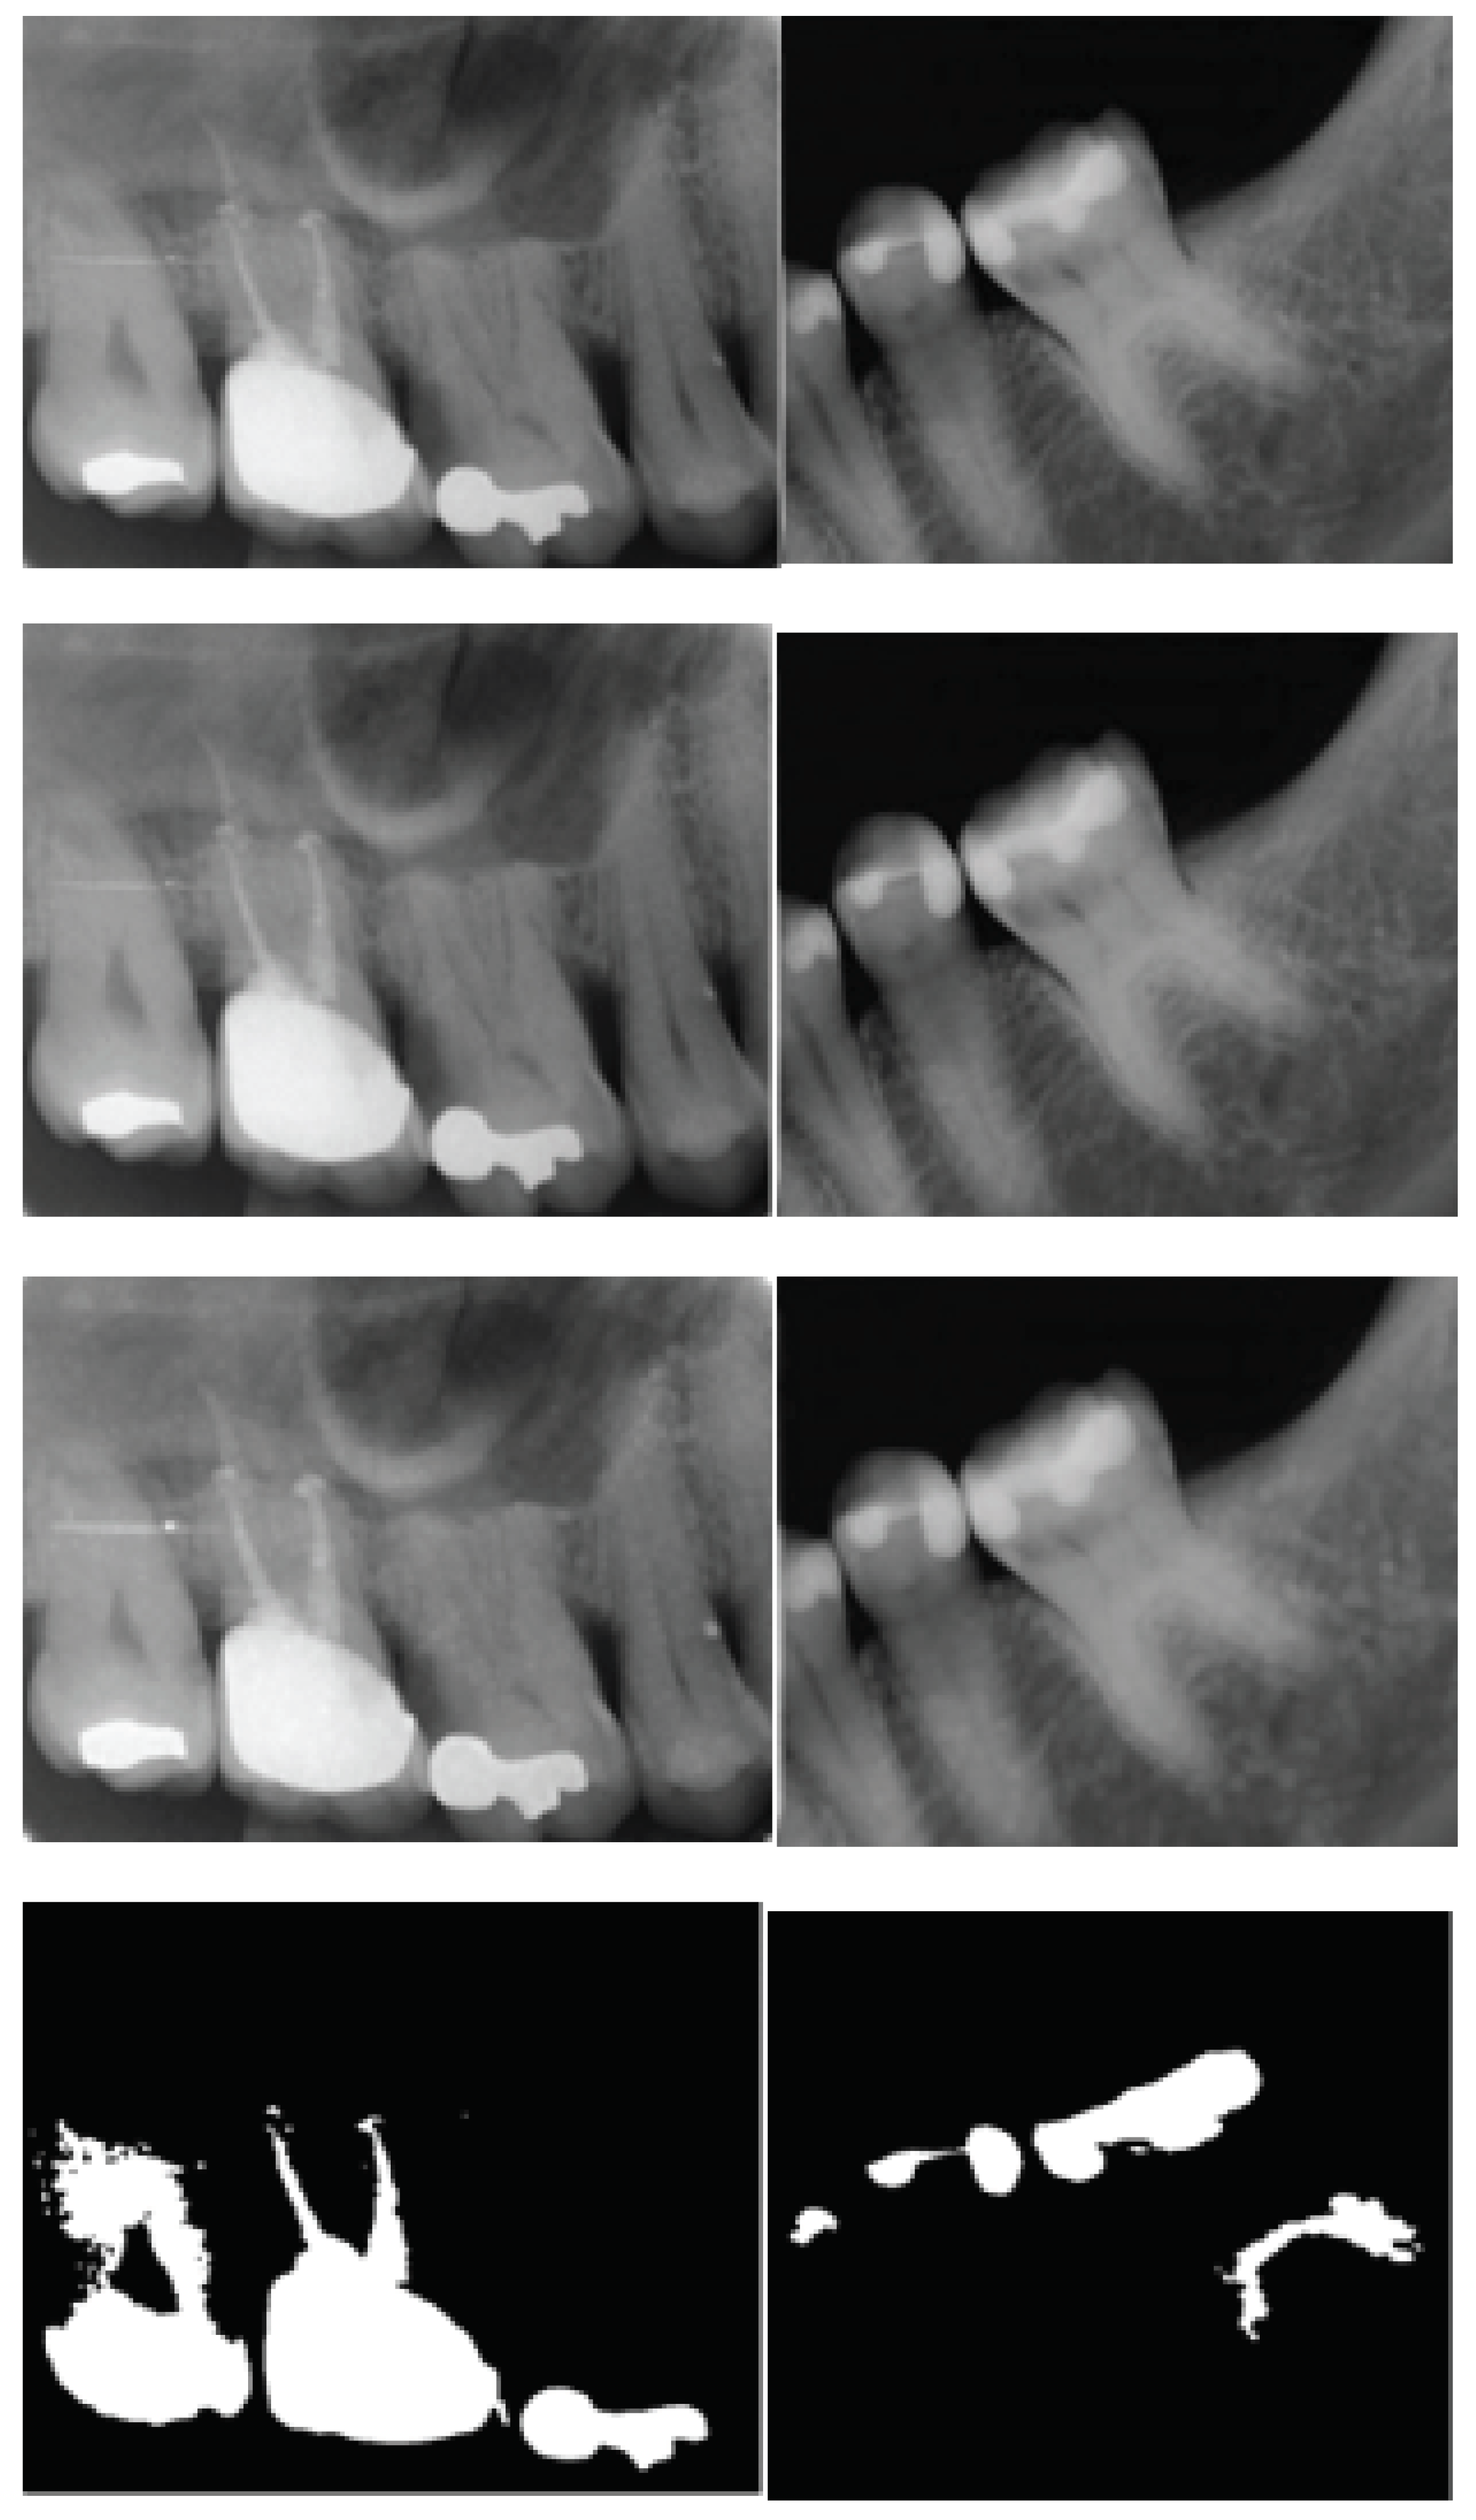

2.1. Pre-Processing of Dental Images

2.2. Segmentation of Images